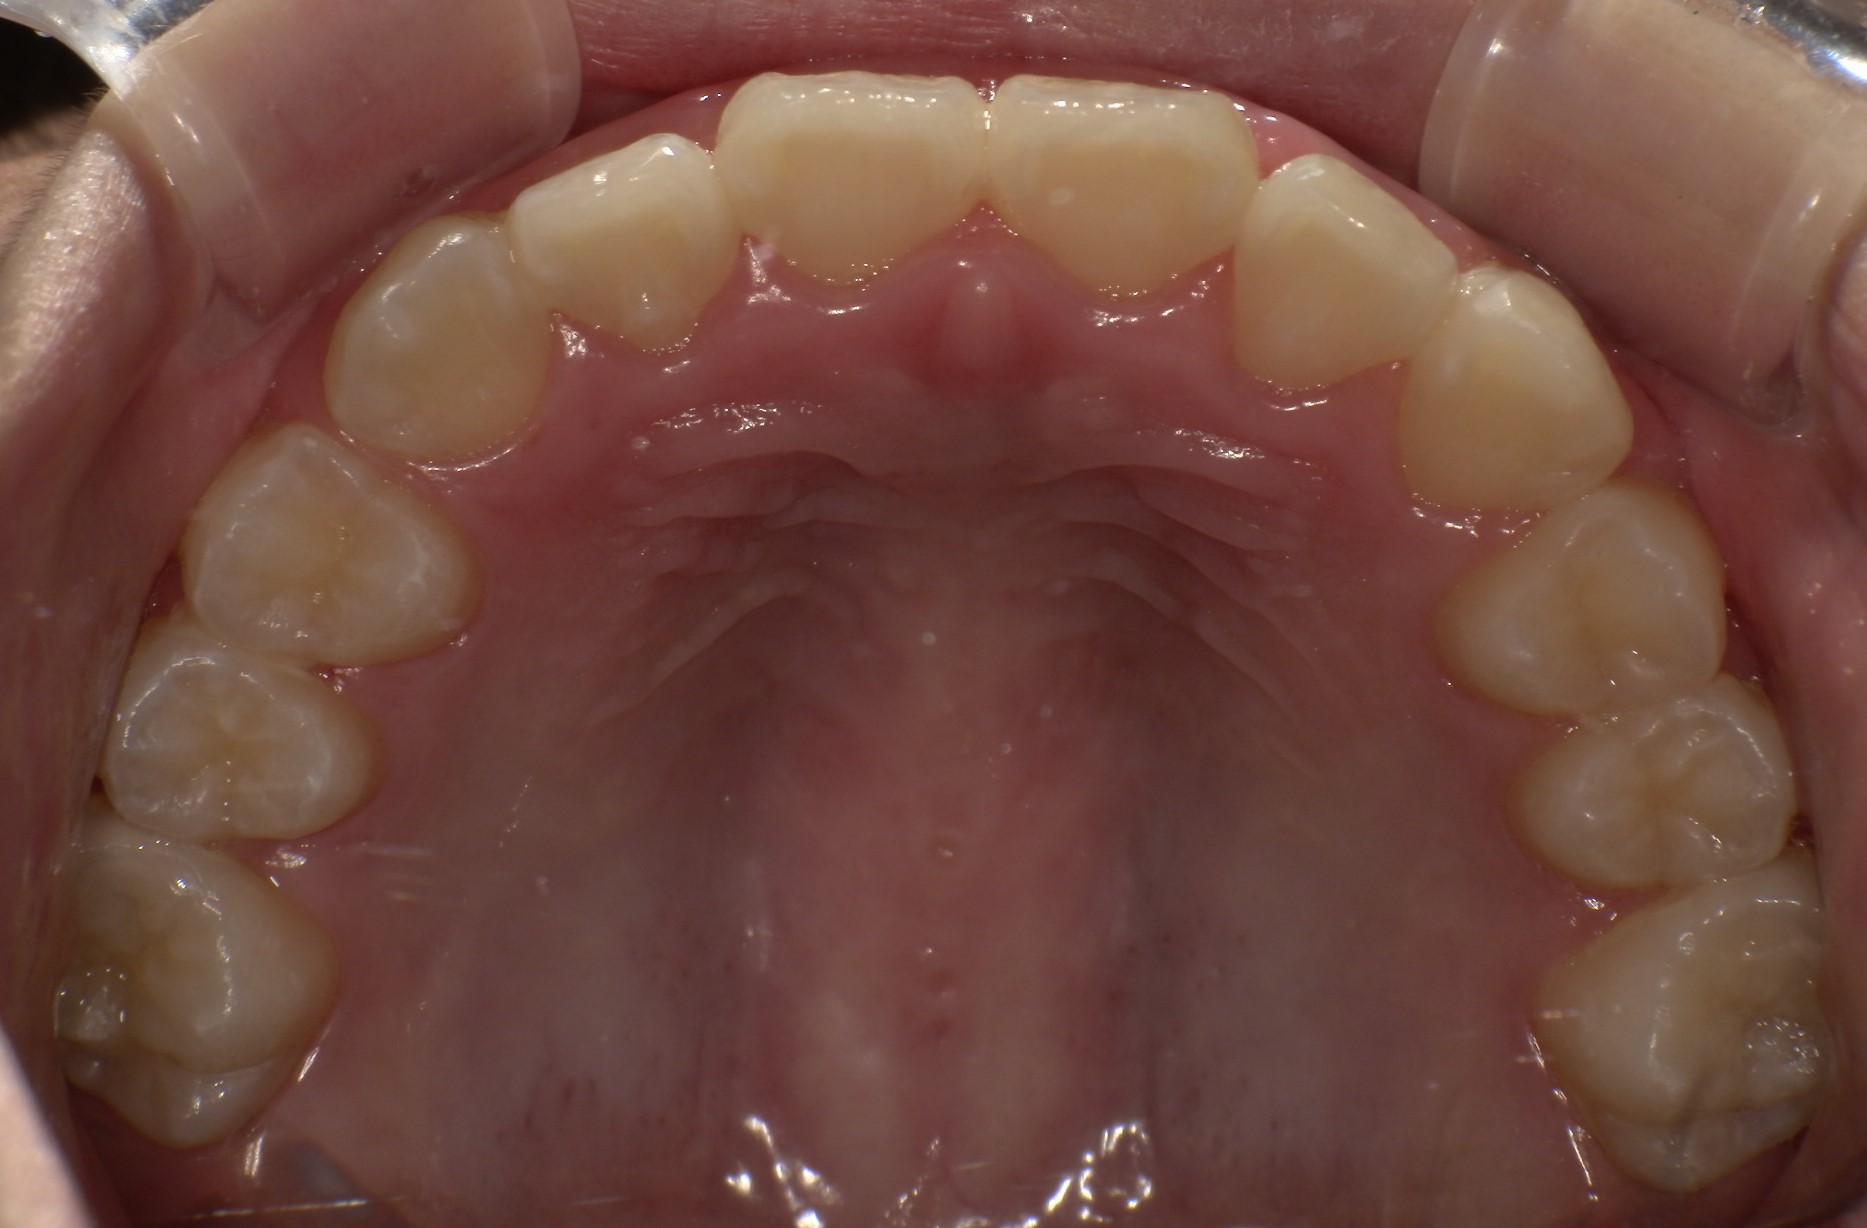

早期矯正治療 叢生症例② 翼状捻転

主訴 | 歯並びの乱れを気にされて来院された患者様です。将来的なスペース不足と歯のねじれ(翼状捻転)が懸念されました。 |

---|---|

診断結果 | 8歳9か月の女児。 歯列全体に叢生(乱れ)が認められました。翼状捻転による咬合不調も確認されています。 |

治療内容 |

|

治療後の経過 | 動的治療は2年10か月で終了後も3〜4か月ごとに定期検診を実施し、上下顎骨の成長発育が落ち着いてから本格矯正治療を行います。 |

治療期間 | 動的治療期間:2年10か月 通院回数:19回 |

治療費用 | 430,000円(税別) |